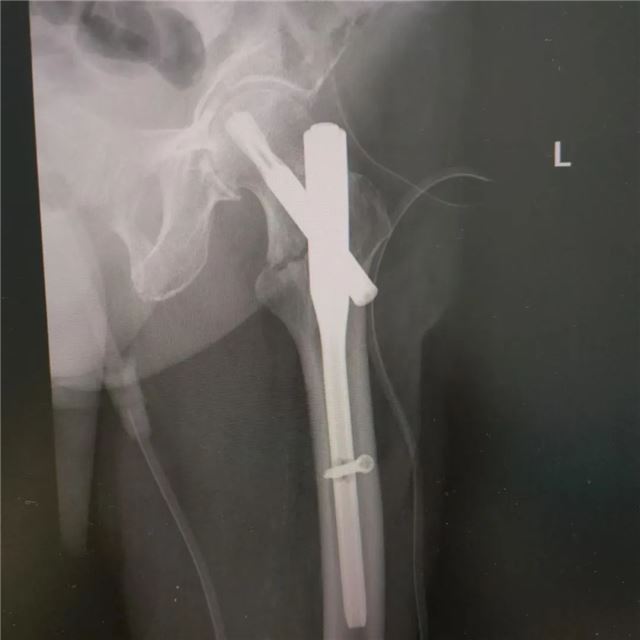

一位102岁的超高龄患者,在家中不慎摔倒,造成左侧股骨粗隆间粉碎性骨折(髋关节部位骨折),髋关节疼痛、活动受限不适,无法负重、站立行走。这是一场对生命的严峻考验。

面对超高龄患者骨折带来的重重困难与治疗风险,内江市第二人民医院骨科医生团队凭借精湛医术和丰富经验,深入研讨制定手术方案,在患者入院第一时间,召开MDT多学科联合会诊,为患者制定了个性化治疗策略和手术方案——左侧股骨粗隆间骨折闭合复位PFNA内固定术。

手术过程中,麻醉医师精准控制麻醉剂量,确保老人生命体征平稳;骨科创伤组长、副主任医师肖伟主刀以沉稳细腻的操作,精准复位患者骨折部位,行闭合复位显示对位对线复位良好,微创手术内牢固固定,三个小切口缝合6针,术中患者仅失血约30ml,全程手术时长28分钟。